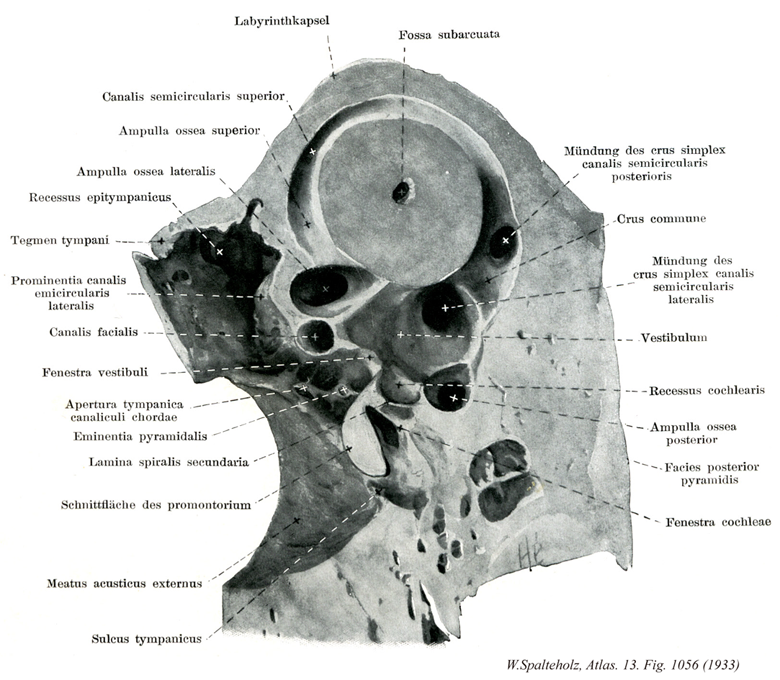

Spalteholz HANDATLAS DER ANATOMIE DES MENSCHEN VON WERNER SPALTEHOLZ

1056

- 1056_00【Temporal bone側頭骨 Os temporale】 Bone located between the occipital, sphenoidal, and parietal bones. It consists of petrous, tympanic, and squamous parts.

→(側頭骨は頭蓋の底部および側面にある大きな不規則形の骨。頭蓋側壁の中央部と頭蓋底中央の両側部を作るばかりでなく、骨の中に平衡聴覚器(外耳道・中耳・内耳)を容れる大切な骨である。岩様部(乳突部と錐体)、鼓室部および鱗部の3部が癒合して単一の骨になるのは生後1年ほど経ってからである。3部が合するところの外面には大きい孔がある。これを外耳孔といい、その内方のつづきは外耳道によって鼓室に通ずる。また、外耳孔の上方で鱗部の外側前方に出る頬骨突起は頬骨に達して頬骨弓をつくる。下縁から咬筋が起こる。)

- 1056_01【Bony labyrinth骨迷路 Labyrinthus osseus】 Bony capsule containing the membranous labyrinth.

→(膜迷路を包む骨性の被い。 (Feneis))

- 1056_02【Anterior semicircular canal前骨半規管;前半規管;上骨半規管 Canalis semicircularis anterior; Canalis semicircularis superior】 Anterior (superior) semicircular canal. It shares a common limb with the posterior semicircular canal and is situated vertically, nearly perpendicular to the axis of the petrous part of temporal bone.

→(後[骨]半規管と共通の脚を有し、錐体軸に垂直に近く位置する。 (Feneis))

- 1056_03【Anterior bony ampulla前骨膨大部;前膨大部;上骨膨大部 Ampulla ossea anterior; Ampulla ossea superior】 Anterior ampulla lying directly adjacent to the lateral bony ampulla.

→(前半規管の膨大。外側膨大部の前方すぐ近くにある。 (Feneis))

- 1056_04【Lateral bony ampulla外側骨膨大部;外側膨大部 Ampulla ossea lateralis】 Ampulla lying anteriorly, directly adjacent to the anterior bony ampulla.

→(前[骨]膨大部の前すぐ横にある。 (Feneis))

- 1056_05【Epitympanic recess鼓室上陥凹 Recessus epitympanicus】 Dome of the tympanic cavity above the upper border of the tympanic membrane that arches upward and laterally.

→(鼓膜上縁の上に、上外側へ向けてできた陥凹。 (Feneis))

- 1056_06【Tegmen tympani鼓室蓋 Tegmen tympani】 Roof of the tympanic cavity located lateral to the arcuate eminence.

→(弓状隆起の外前方、錐体鱗裂との間は、鼓室およびその前方につづく筋耳管管の上を被う部で骨質が薄く、これを鼓室蓋という。骨の発育藤生の場合や老人ではここに孔をみることがある。)

- 1056_07【Prominence of lateral semicircular canal外側半規管隆起;外側半規管突隆 Prominentia canalis semicircularis lateralis】 Elevation above the prominence of the facial canal that is produced by the lateral semicircular canal.

→(顔面神経管隆起上方にある隆起。外側半規管によってできる。 (Feneis))

- 1056_08Fallopian canal【Facial canal; Facial nerve canal顔面神経管 Canalis nervi facialis】 Canal for transmission of the facial nerve. It begins at the internal acoustic opening and ends at the stylomastoid foramen.

→(顔面神経管は内耳孔に始まって茎乳突孔に終わる。顔面神経管は顔面神経の通路で、内耳道底にある横稜の顔面神経野にはじまり、まず蝸牛の外側に沿い殆ど水平位で前外方に進み、つぎにほぼ直角をなして後外方に曲がる。ここを顔面神経管膝という。ついで鼓室壁の前庭窓の上を通って少し外後方に進んだ後、下方へ向かって弓状に曲がり(この間、鼓室内側壁に顔面神経管隆起をつくる)、茎乳突孔に開く。この間は膝で1条の枝を出し、骨を貫いて前進し錐体前面の大錐体神経管裂孔を出て大錐体神経溝につづき、大錐体神経管がこれを通る。『フォロッピオ管』:側頭骨錐体にある顔面神経管。イタリアの解剖学者Gabriele Fallopio [Fallopius](1523-1563)によるもので、他にファロピウス管(卵管)にも名を残す。両者を混同しないため、顔面神経管はフォロッピオ管と呼ぶのがふつうである。)

- 1056_09【Oval window; Vestibular window前庭窓;卵円窓 Fenestra vestibuli】 Opening that is closed off by the base of the stapes.

→(前庭窓は鼓室の内側壁の卵形開口で、前庭に通じ生体ではこの窓にアブミ骨底がはまりこんでいる。前庭窓のすぐ下に岬角とよばれる隆起がある。)

- 1056_10【Tympanic aperture of canaliculus for chorda tympani鼓索小管鼓室口 Apertura tympanica canaliculi (Chordae tympani)】 Opening into the tympanic cavity lying at the posterior margin of the tympanic membrane at the level of the pyramidal eminence.

→(錐体隆起の高さで鼓膜後縁にある。 (Feneis))

- 1056_11【Pyramidal eminence錐体隆起 Eminentia pyramidalis】 Conical, bony prominence at the level of the oval window with a perforated summit. It contains the stapedius and gives its tendon exit through the opening at its tip.B

→(前庭窓の高さにある尖端に孔のあいた隆起。アブミ骨筋を有し、尖端の開口部より腱がでる。 (Feneis))

- 1056_12【Secondary spiral lamina第2ラセン板 Lamina spiralis secundaria】 Bony ridge situated in the lower half of the basal turn of the cochlea. It projects from the lateral wall of the spiral canal of cochlea opposite to the osseous spiral lamina. The inferior portion of the basal lamina is stretched between the two.

→(基底回転の下半分にかる骨性板。蝸牛ラセン管の外側壁により起こり、骨ラセン板に向かい合う位置にある。両者の間に下部基底板が張る。 (Feneis))

- 1056_13【Promontory of tympanic cavity岬角(鼓室の) Promontorium (Tympani)】 Elevation produced by the basal turn of the cochlea.

→(蝸牛の基底回転によりできる隆起。 (Feneis))

- 1056_14【External acoustic meatus; External auditory meatus外耳道 Meatus acusticus externus】

→(外耳道は側頭骨の鼓室部を耳介から鼓膜へ至る通路で骨性部分。軟骨性外耳道からなる。)

- 1056_15【Tympanic sulcus鼓膜溝;鼓室輪溝 Sulcus tympanicus; Sulcus anuli tympanici】 Groove that provides attachment to the tympanic membrane.

→(鼓膜が付着する溝。(Feneis))

- 1056_16【Subarcuate fossa弓下窩;弓状下窩 Fossa subarcuata】 Depression located posterosuperior to the internal acoustic meatus for the fetal flocculus.

→(内耳孔の後外方には上縁に近く浅い弓下窩がある。脳硬膜が付着するところで、小児に著しい。)

- 1056_17【Simple bony limb of semicircular canal骨単脚(骨半規管の) Crus osseum simplex canalis semicircularis】 Posterior limb of the lateral semicircular canal that opens alone into the wall of the vestibule.

→(外側[骨]半規管が単独で前庭へ開口する脚。 (Feneis))

- 1056_18【Posterior semicircular canal後骨半規管;後半規管 Canalis semicircularis posterior】 Canal situated furthest to inferior. It is situated nearly parallel to the axis of the petrous part of temporal bone.

→(最も下方に位置する半規管、錐体軸に平行に位置する。 (Feneis))

- 1056_19【Common bony limb of semicircular canal骨総脚(骨半規管の) Crus osseum commune canalis semicircularis】 Posterior limb formed by the union of the limbs of the anterior (superior) and posterior semicircular canals.

→(前および後[骨]半規管の脚の合一により生じた脚。 (Feneis))

- 1056_20【Lateral semicircular canal外側骨半規管;外側半規管 Canalis semicircularis lateralis】 It lies horizontally and ca. produce a prominence in the medial wall of the tympanic cavity.

→(水平に位置し、鼓室内側壁へ隆起をつくることもある。 (Feneis))

- 1056_21【Vestibule前庭(内耳の) Vestibulum labyrinthi】 Portion of the bony labyrinth containing the utricle and saccule.

→(骨迷路の一部。卵形嚢および球形嚢を含む。 (Feneis))

- 1056_22【Cochlear recess蝸牛陥凹 Recessus cochlearis】 Depression situated beneath and anterior to the spherical recess. It lodges the inferior end of the cochlear duct.

→(球形嚢陥凹の下および前方にあるくぼみ。蝸牛管の下端をおさめる。 (Feneis))

- 1056_23【Posterior bony ampulla後骨膨大部 Ampulla ossea posterior】 Posterior ampulla lying beneath the level of the lateral semicircular canal.

→(外側半規管のつくる面の下後方にある。 (Feneis))

- 1056_24【Posterior surface of petrous part錐体後面;錐体小脳面(側頭骨の) Facies posterior partis petrosae; Facies posterior pyramidis; Facies cerebellaris pyramidis】

→(側頭骨の上後面を錐体後面という。そのほぼ中央にある楕円形の内耳孔は、後外側に向かって骨内に入る内耳道につづく。)

- 1056_25【Round window; *Cochlear window蝸牛窓;正円窓 Fenestra cochleae】 Round opening at the end of the scala tympani that is closed off by the secondary tympanic membrane.

→(蝸牛窓は中耳の内壁にある孔で、蝸牛に開くが、生体ではあぶみ骨底にによって閉ざされている。結合組織性の第二鼓膜が張っている。第二鼓膜は臨床医に正円窓膜とよばれる薄い膜で、中耳側より内耳側に向かって鼓膜層、固有層、内層の3層から成っている。粘膜層は鼓室の粘膜層のつづきであり、固有層は結合組織からなり、内層は外リンパ隙に面する内皮から成るが、明瞭な細胞層を呈していない。また前庭の内側(鼓室と反体側)から側頭骨錐体の後面へ前庭膵管とよばれる細い管が通っている。前庭水管の中は膜迷路である内リンパ管が通っている。)